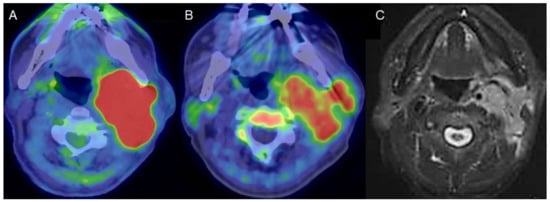

Figure 1.

A man in his 80s with carcinoma arising in the left parotid gland. (A) Fused FDG-PET/CT image (axial view), (B) fused 4DST PET/CT image (axial view), and (C) gadolinium (Gd)-enhanced MRI (axial view). Gd-enhanced MRI shows homogeneous enhancement of an irregular-shaped lesion in the left parotid gland. High FDG uptake (SUVmax: 21.8) as well as lower, but unequivocal, 4DST uptake (SUVmax: 6.0) were confirmed in the lesion.